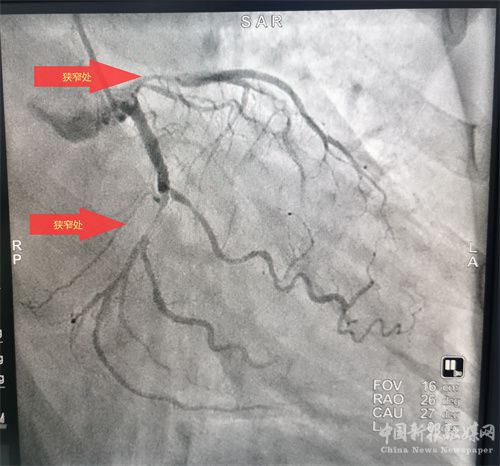

患者溶栓成功后,經(jīng)患者及家屬同意后行冠狀動(dòng)脈造影檢查,患者冠脈顯示前降支次全閉、回旋支狹窄95%、右冠近端狹窄85%,病情緊急,李維軍、楊亮主任向家屬詳細(xì)講明病情后,予以開通前降支和回旋支,植入支架3枚。手術(shù)全程用時(shí)不到一個(gè)小時(shí)。目前,患者病情穩(wěn)定。